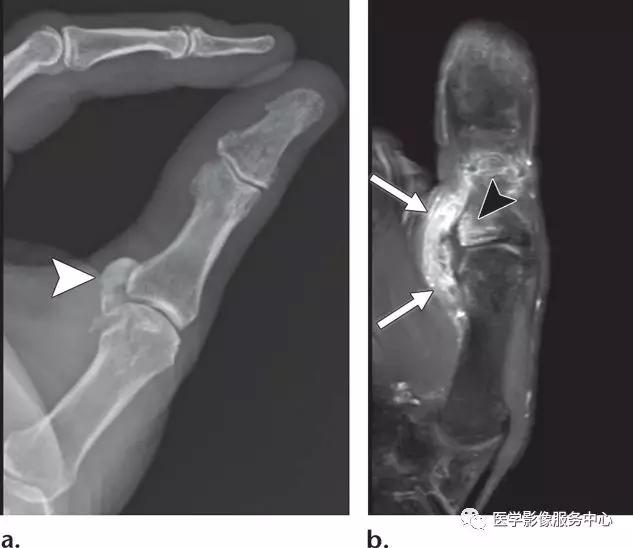

尺侧副韧带的撕脱损伤:

(左)第一指骨近端尺侧的尺侧副韧带撕脱骨折。

(中)白色箭头显示尺侧副韧带的全层紊乱,尺侧副韧带的正常解剖关系是位于内收肌腱膜(黑色箭头)的深部。

(右)Stener病变,伴尺侧副韧带损伤,撕脱的骨片被牵拉回缩(白色箭头)。